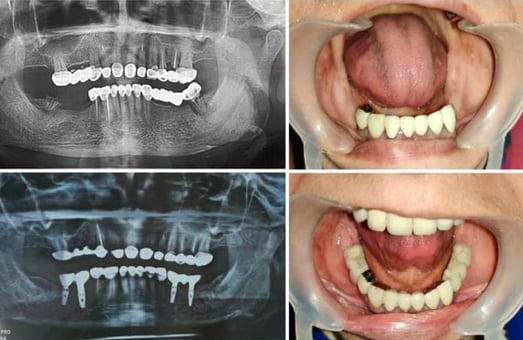

Full mouth implant cases in affordable treatment option

FIX TEETH WITH DENTAL IMPLANTS

Revolutionize Your Smile with Dental Implant